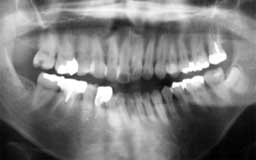

Nさん 初診時 51歳 女性

10年以上前からメインテナンスを受けていたということで、治療済みの歯や虫歯が多いもの の、歯周組織の状態は良好

Nさん 20年後 71歳

金属の被せが非常に目立ちますが、28本すべて健在は立派です